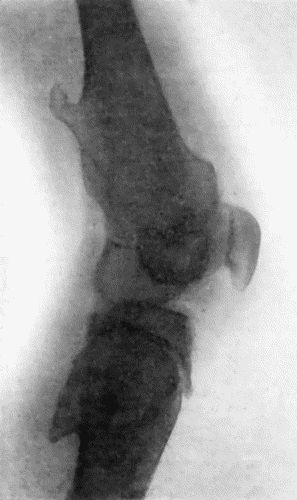

Another modification is to raise the flap but leave it connected at both ends like the piers of a bridge; this method is well suited to defects of skin on the dorsum of the fingers, hand and forearm, the bridge of skin is raised from the abdominal wall and the hand is passed beneath it and securely fixed in position; after an interval of 14 to 21 days, when the flap is assured of its blood supply, the piers of the bridge are divided (Fig. 1). With undermining it is usually easy to bring the edges of the gap in the abdominal wall together, even in children; the skin flap on the dorsum of the hand appears rather thick and prominent—almost like the pad of a boxing-glove—for some time, but the restoration of function in the capacity to flex the fingers is gratifying in the extreme.

Fig. 1.—Ulcer of back of Hand covered by flap of skin raised from anterior abdominal wall. The lateral edges of the flap are divided after the graft has adhered.